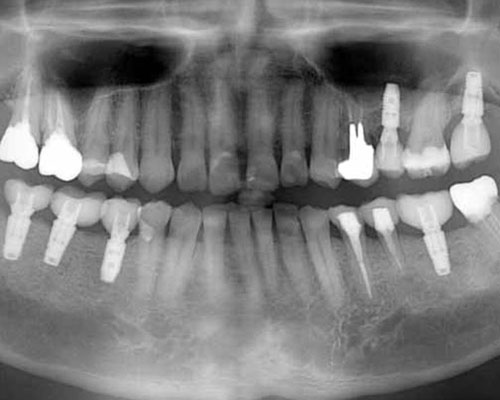

2本目のインプラント

右側に1本インプラントの仮歯が入ったので、代わりに左上を1本抜かせてもらい、右下に2本目のインプラントを入れました。この時点では、まだ左側を中心食事をされていたそうです。ちょっと一安心ですね。